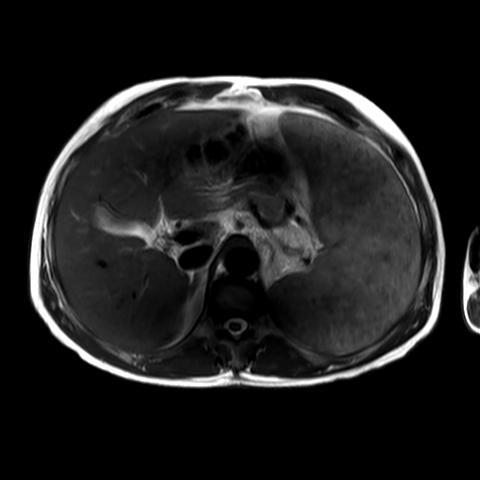

Marked splenomegaly with multiple splenic foci of low signal, they are tiny innumerable (Gamna Gandy bodies).

Case Discussion

Splenic siderotic nodules (also known as Gamna-Gandy bodies) of the spleen is most commonly encountered in portal hypertension. The pathophysiological process is the result of microhaemorhage resulting in haemosiderin and calcium deposition followed by fibroblastic reaction.